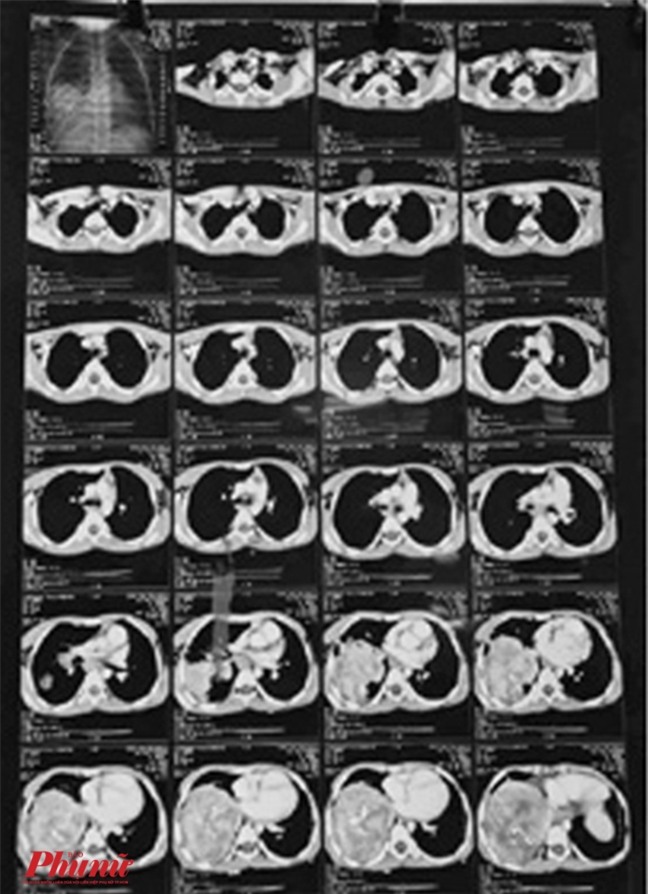

Sau khi làm các xét nghiệm, chụp cắt lớp điện toán (CT) các bác sĩ phát hiện trong lồng ngực bé K. có một khối u "khủng" nằm ở thùy dưới của phổi phải. Khối u chiếm gần hết khoang lồng ngực của bé, chèn ép tim.

Khối u gần như chiếm hết phổi của bé K.